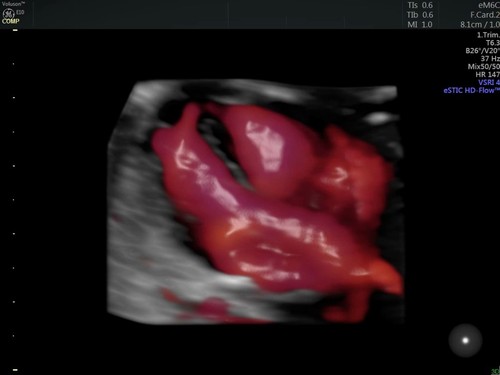

По словам Барбары Дель Принс, самая современная система GE Voluson E10* способна испускать сигналы и обрабатывать информацию достаточно быстро для просмотра работы сердца в режиме реального времени. «Эта система поможет врачам раньше поставить точный диагноз», — отмечает Барбара.

Снимок развития сердца, сделанный в первый триместр беременности с помощью приложения HDlive Flow.

Снимок развития сердца, сделанный в первый триместр беременности с помощью приложения HDlive Flow.Подобным быстродействием система обязана новым датчикам, изготовленным по технологии Electronic 4D. В датчике установлены более 8000 пьезокристаллов для электронного управления ультразвуковым пучком и обеспечения четкости и скорости.

Неподвижное изображение ноги, полученное с помощью ультразвука в режиме 4D в приложении HDlive Silhouette.Еще одна функция программного обеспечения HDlive Flow — это создание 3D-изображения потока крови и фотореалистичного изображения кровеносных сосудов. «Такая возможность очень важна для врачей, когда они рассматривают патологические изменения, — говорит Барбара Дель Принс. — Однако большинство родителей, скорее всего, просто запомнят первую улыбку своего ребенка».